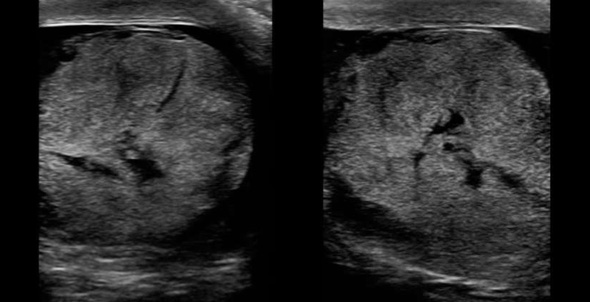

- A coronal scan showing both testicles side by side should be performed to identify differences in size and echogenicity, and vascularity. (Figure 2)

Figure 2. Also known as the ‘buddy’ or ‘spectacle’ view, a coronal scan showing both testicles side by side allows for comparison in size, relative echogenicity and blood flow.